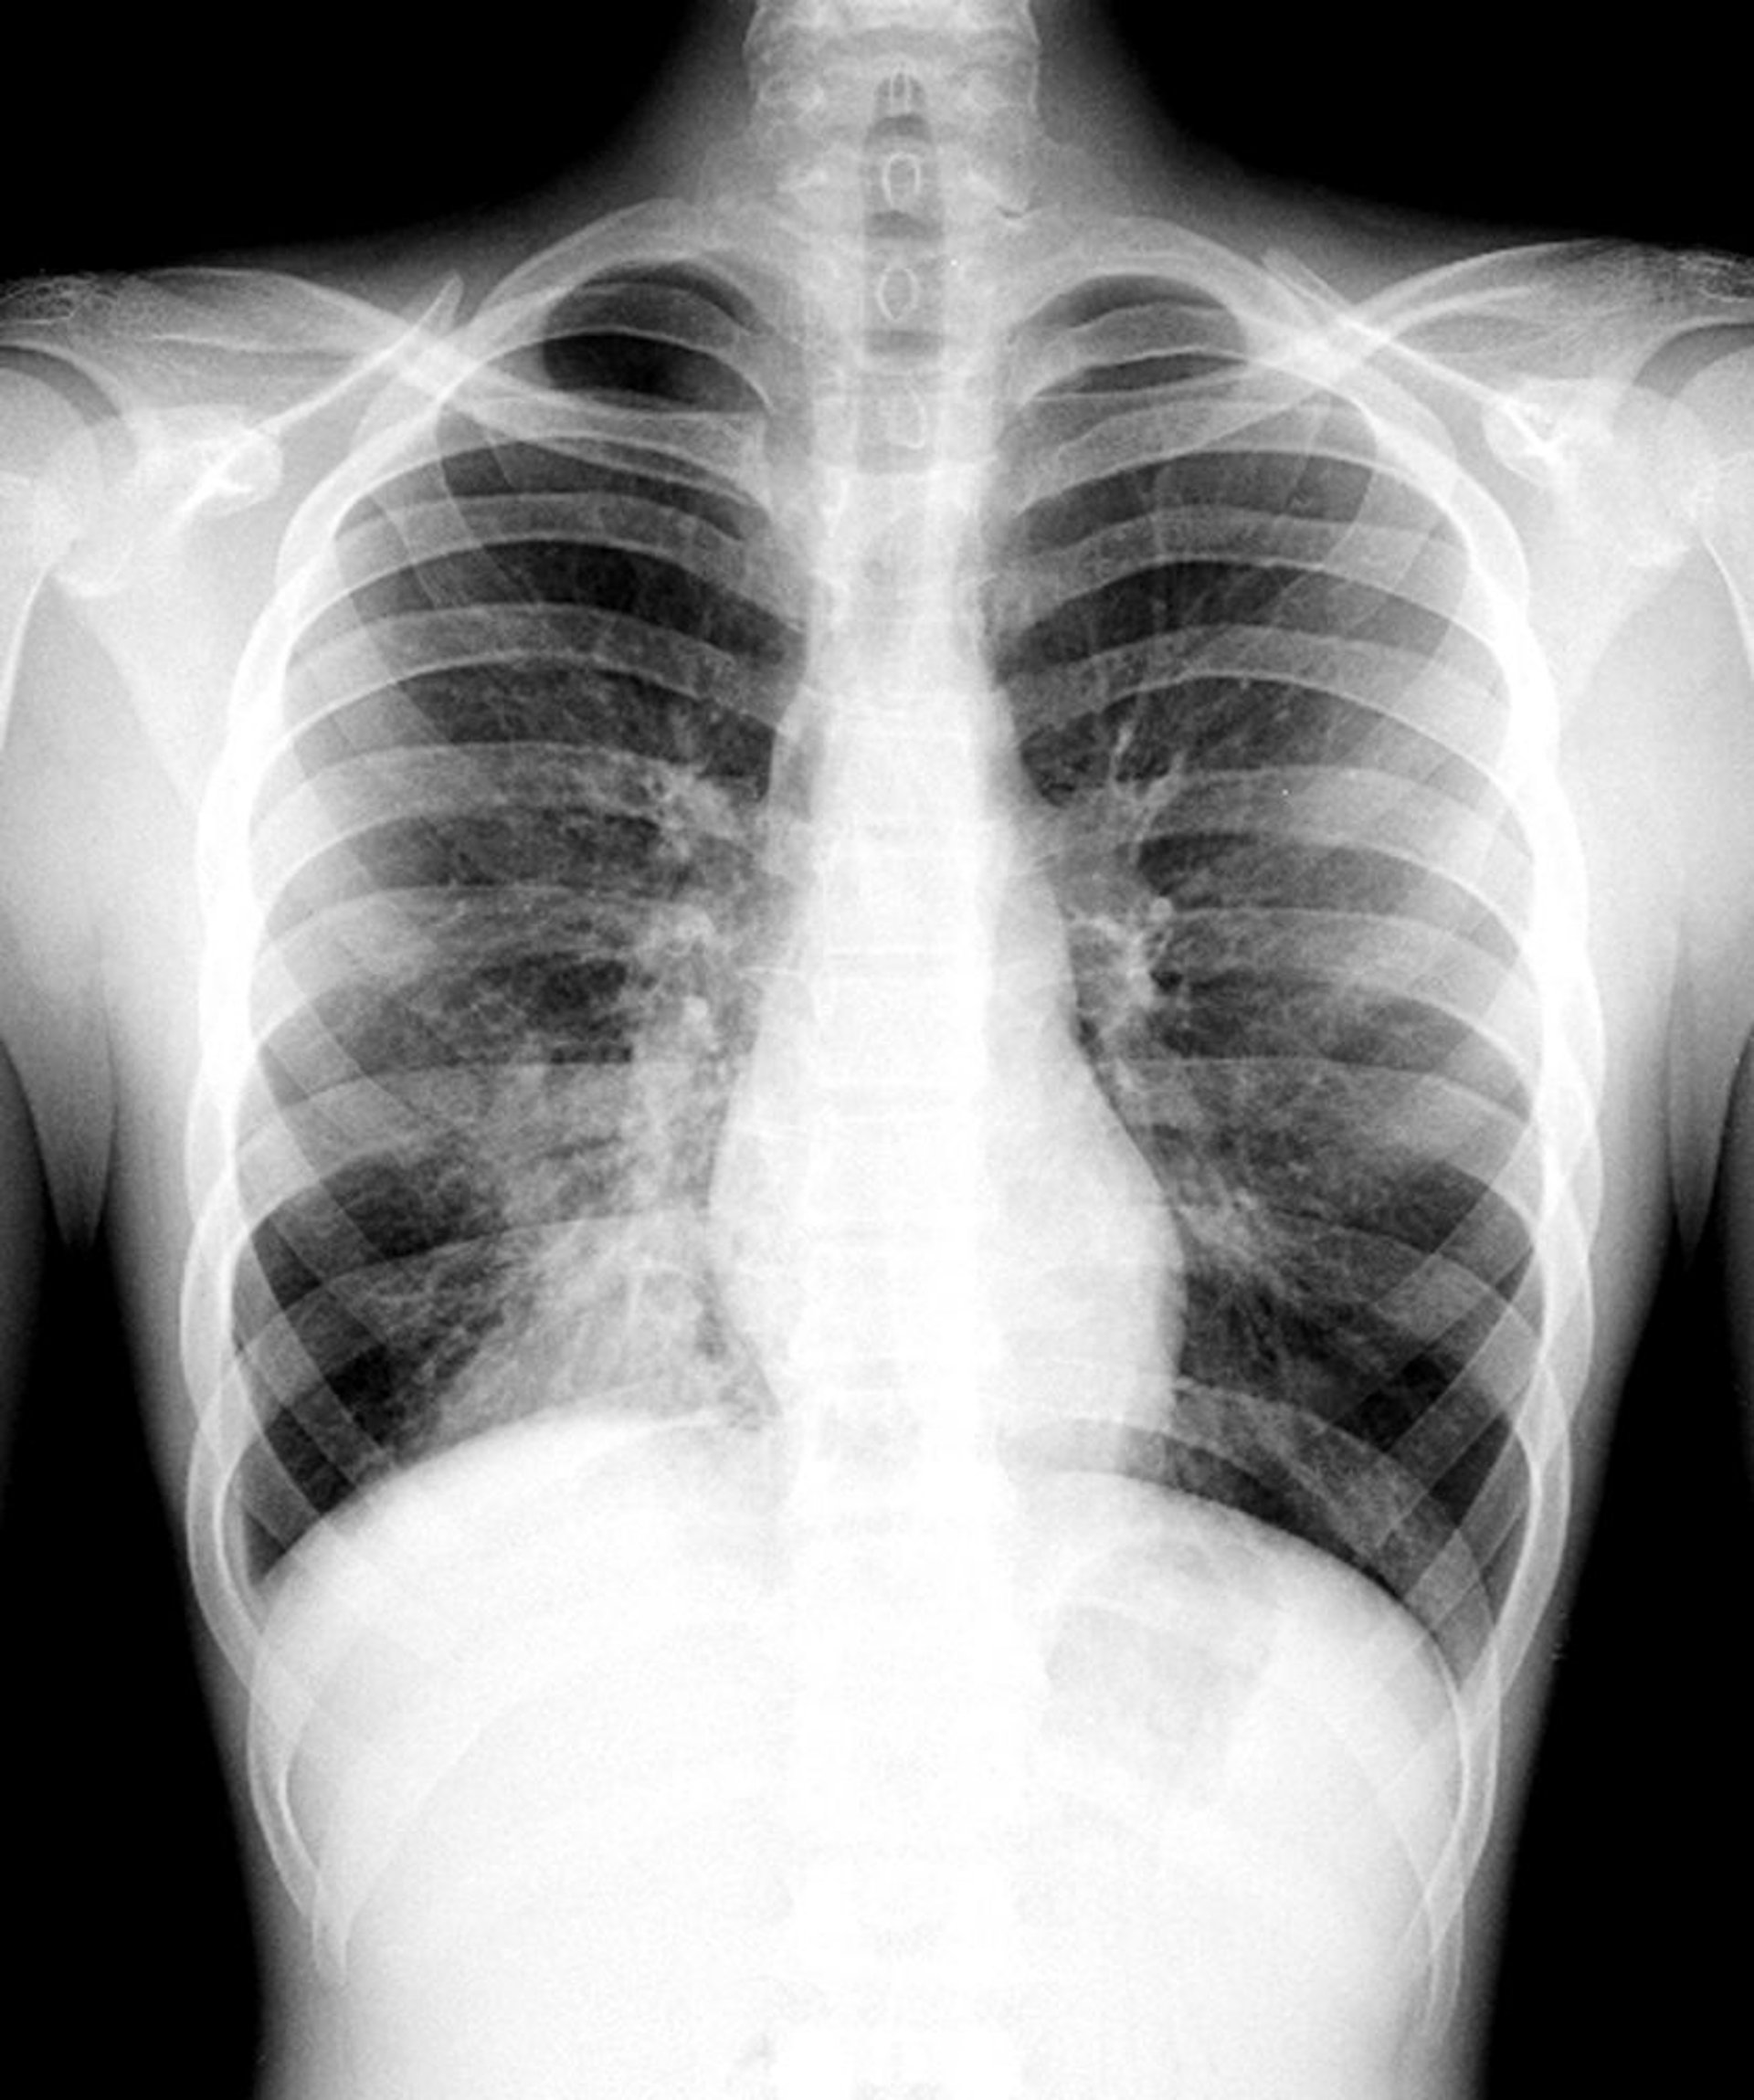

Pneumonie du lobe inférieur droit

Cette radiographie pulmonaire montre un infiltrat qui ne masque pas le bord droit du cœur (c'est-à-dire, il n'y a pas de signe de silhouette). Le signe de la silhouette se développant lorsque 2 structures contiguës ont une radiodensité similaire, la partie du poumon affectée par cet infiltrat est la partie non contiguë au bord droit du cœur; cette partie est le lobe inférieur droit.